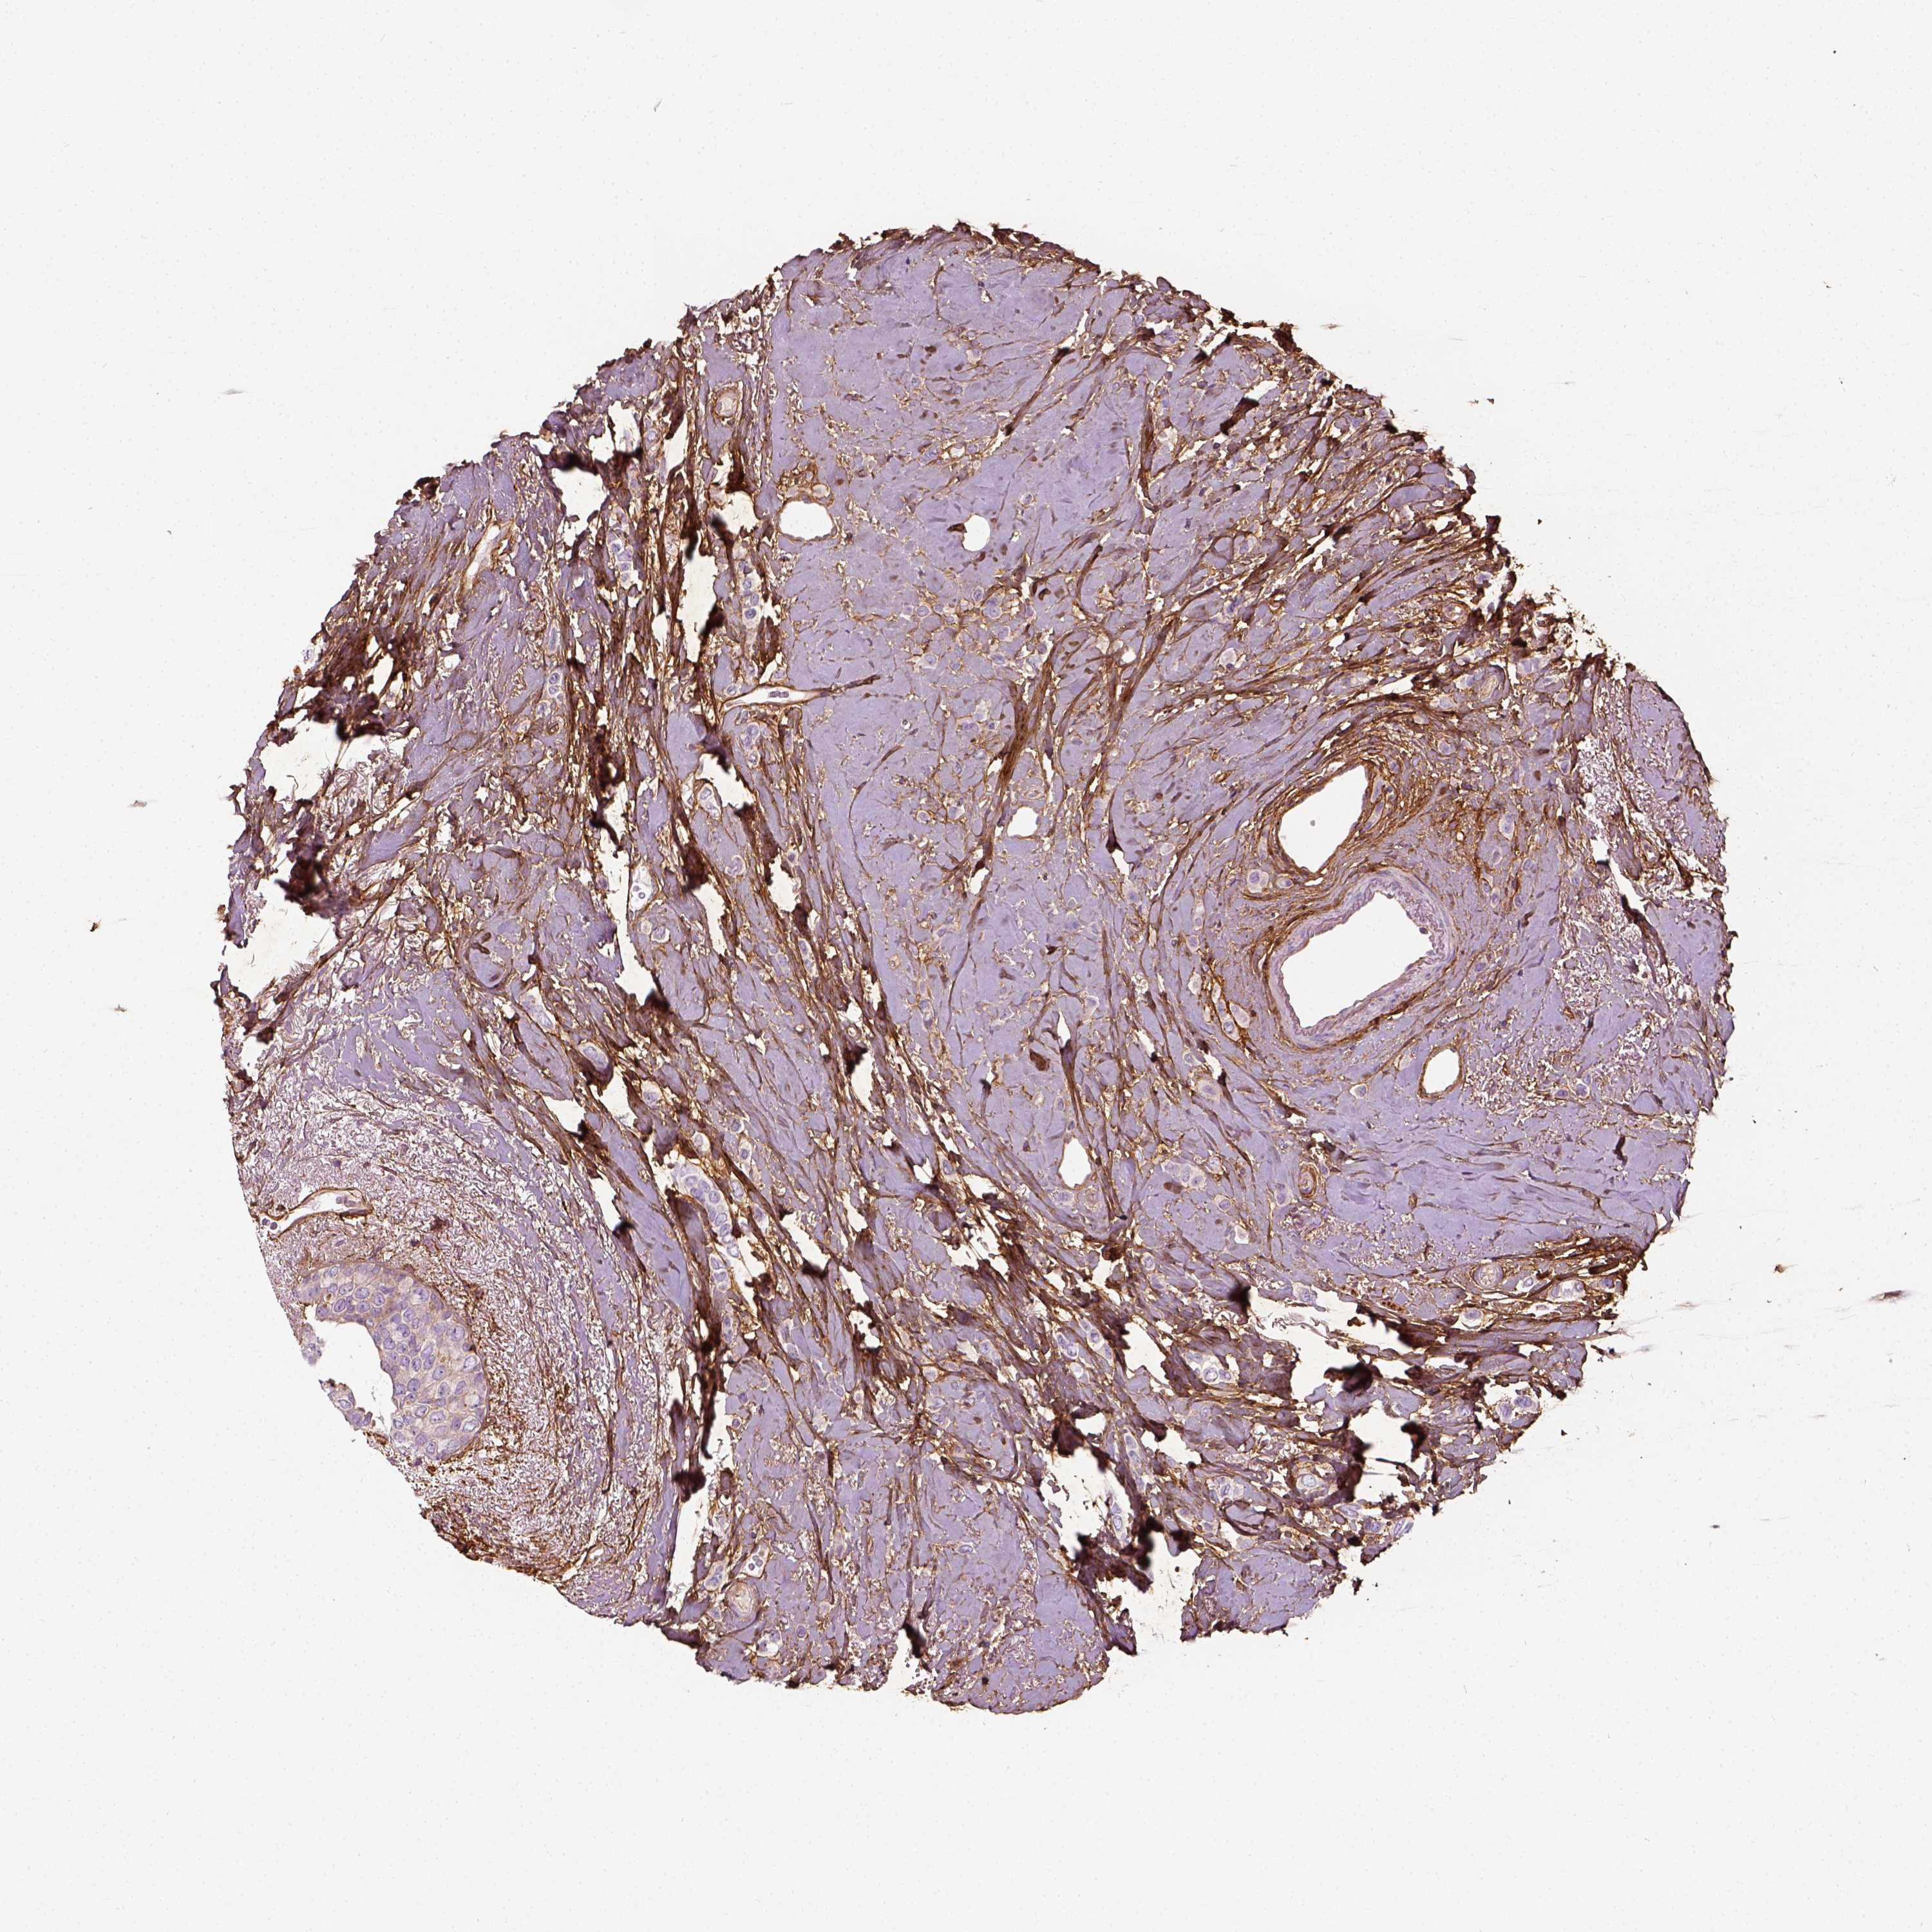

CANCER BREAST CANCER Show tissue menu

Breast cancer

Human cancer